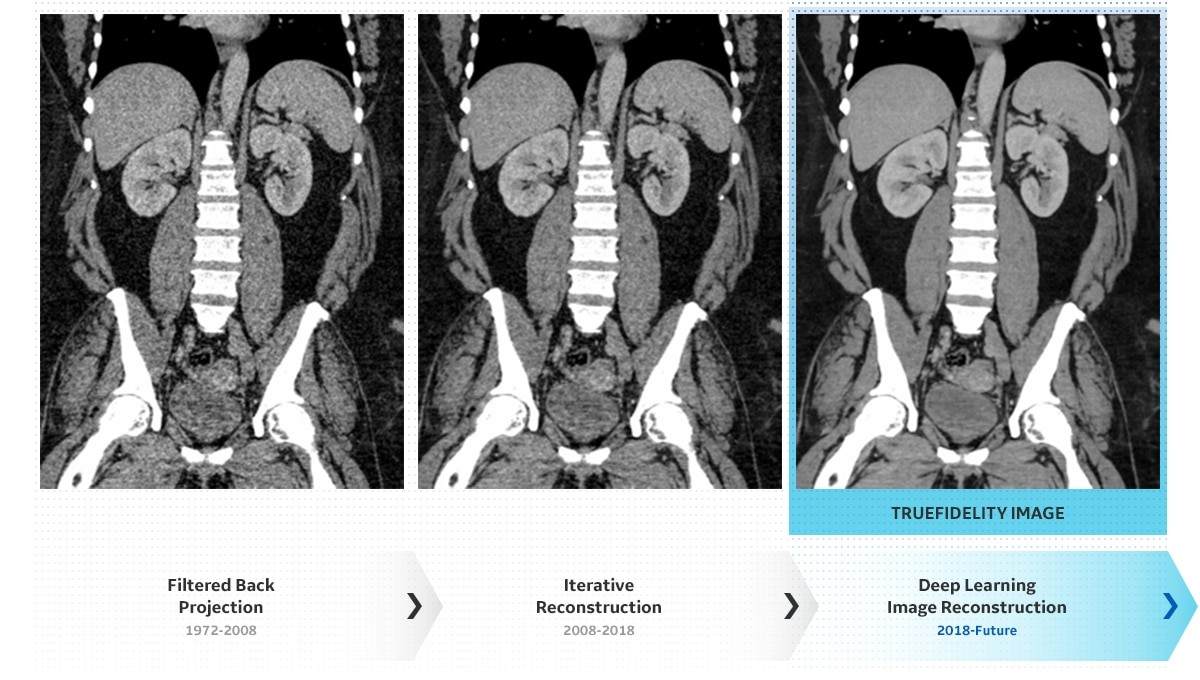

智能设备——兼顾低剂量与高画质的人工智能CT图像处理技术TrueFidelity™:在Edison平台上通过深度神经网络训练开发出TrueFidelityTM,是业界首个还原原始图像的深度学习CT影像重建算法。通过持续学习超过一百万高射线剂量条件下的高清真实影像,TrueFidelityTM在更低射线剂量下,重建扫描影像,去除伪影与噪声,还原图像的真实纹理,为医生提供更有利于精准诊断的信息,减少漏诊的可能性。应用在武汉雷神山医院 “深度天眼”CT便搭载了这一技术。TrueFidelityTM技术配合AI自动患者摆位,“深度天眼” 仅需三步即可完成整个CT扫描前的操作。临床对比结果显示,可单个患者可节省30%的扫描时间,提升50%的病灶检出率。